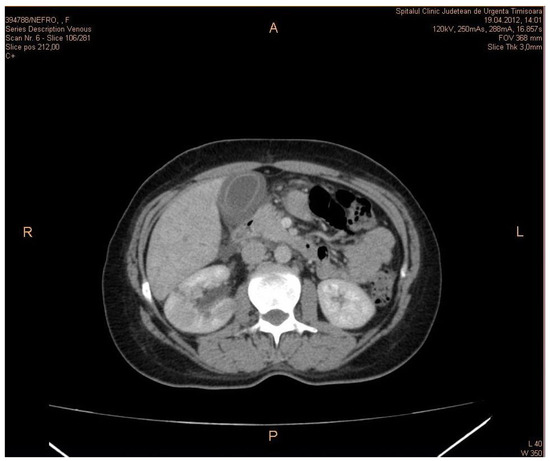

A contrast-enhanced CT scan of a patient showing kidney abscesses associated with ACC is presented in Figure 1.

Figure 1. Contrast-enhanced CT scan of a patient in the venous phase showing kidney abscesses associated with acute acalculous cholecystitis.

CT is the best technique to evaluate the disease. MRI can be the modality of choice for patients allergic to iodine contrast media. Non-contrast axial CT image showing a right renal hypodense mass of fluid attenuation is indicative of disease. Contrast-enhanced axial CT image showing a right renal mass with more extensive areas of cortical hypoenhancement and cortical and subcapsular fluid collections is indicative of disease. Perinephric stranding and inflammation are present without right hydronephrosis.